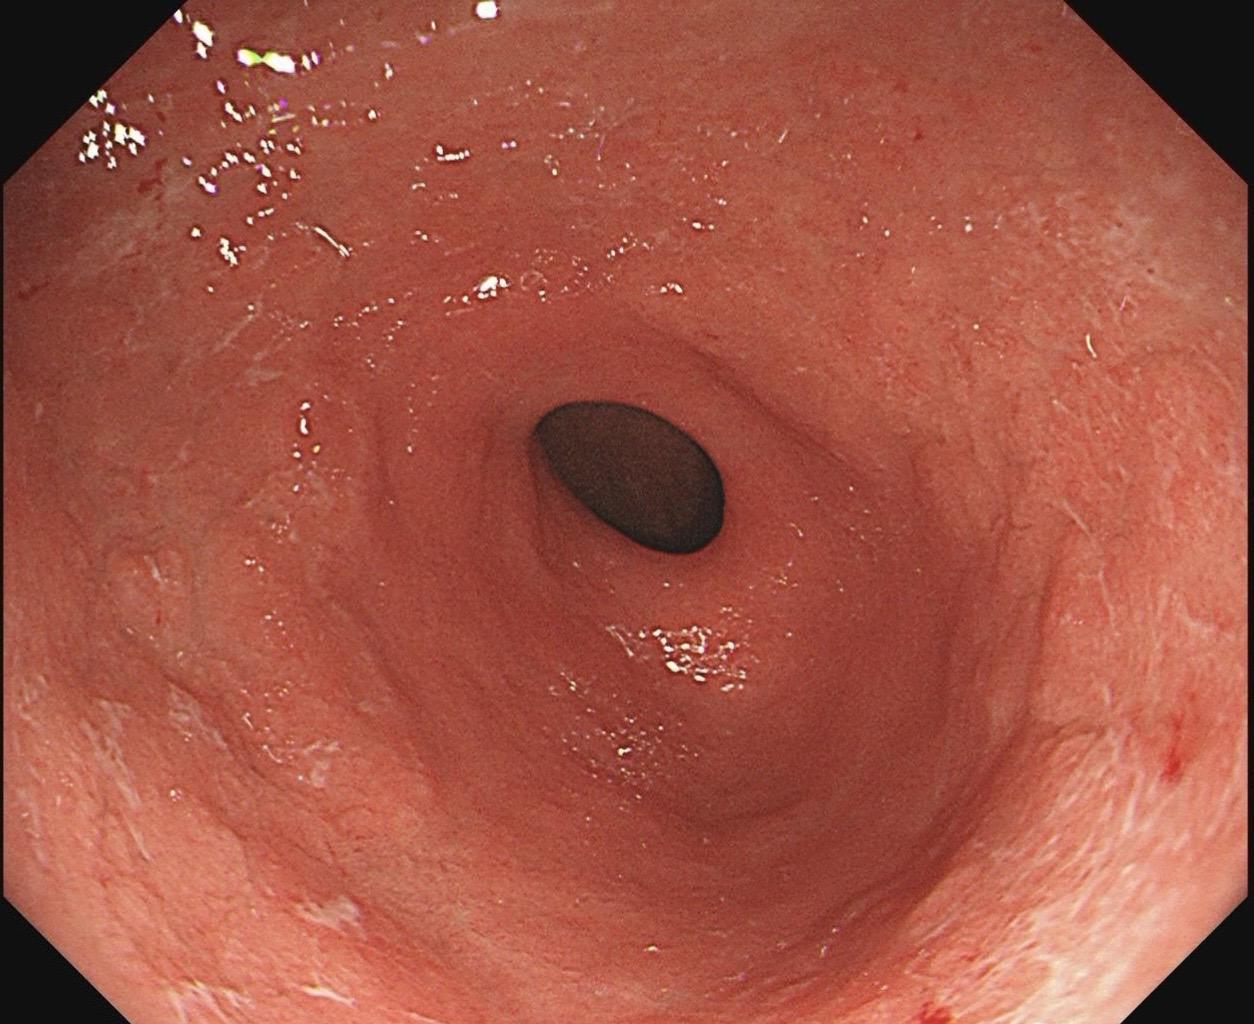

男,61岁,胃巨大褪色调病变。答案在最后一张图片,你猜对了吗? 患者因上腹部饱胀行胃镜检查,Hp阴性背景,胃窦至贲门下见一巨大褪色调病变,边界清晰,病变相对表浅,未见明显溃疡及隆起,胃壁较柔软,充气顺应性佳,予多点活检确诊,拟外科手术行全胃切除。做这么多年胃镜,还是第一次遇到这样的……